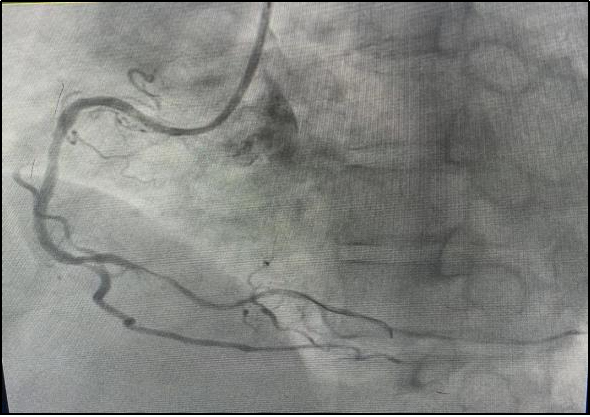

“发热”对于大家来说应该都不陌生吧?但是仅有发热症状的急性心肌梗塞大家听过吗?近日,我院急诊医生在接诊时细心观察,及时发现一名仅有发热症状的急性心肌梗塞患者,并通过介入手术成功挽救其生命。

黄叔基础血压较高,血压基本都在160/90mmHg以上,本次就诊时血压虽然看上去处于正常范围,但血压在短时间内下降超过30%,提示可能存在休克的状态。